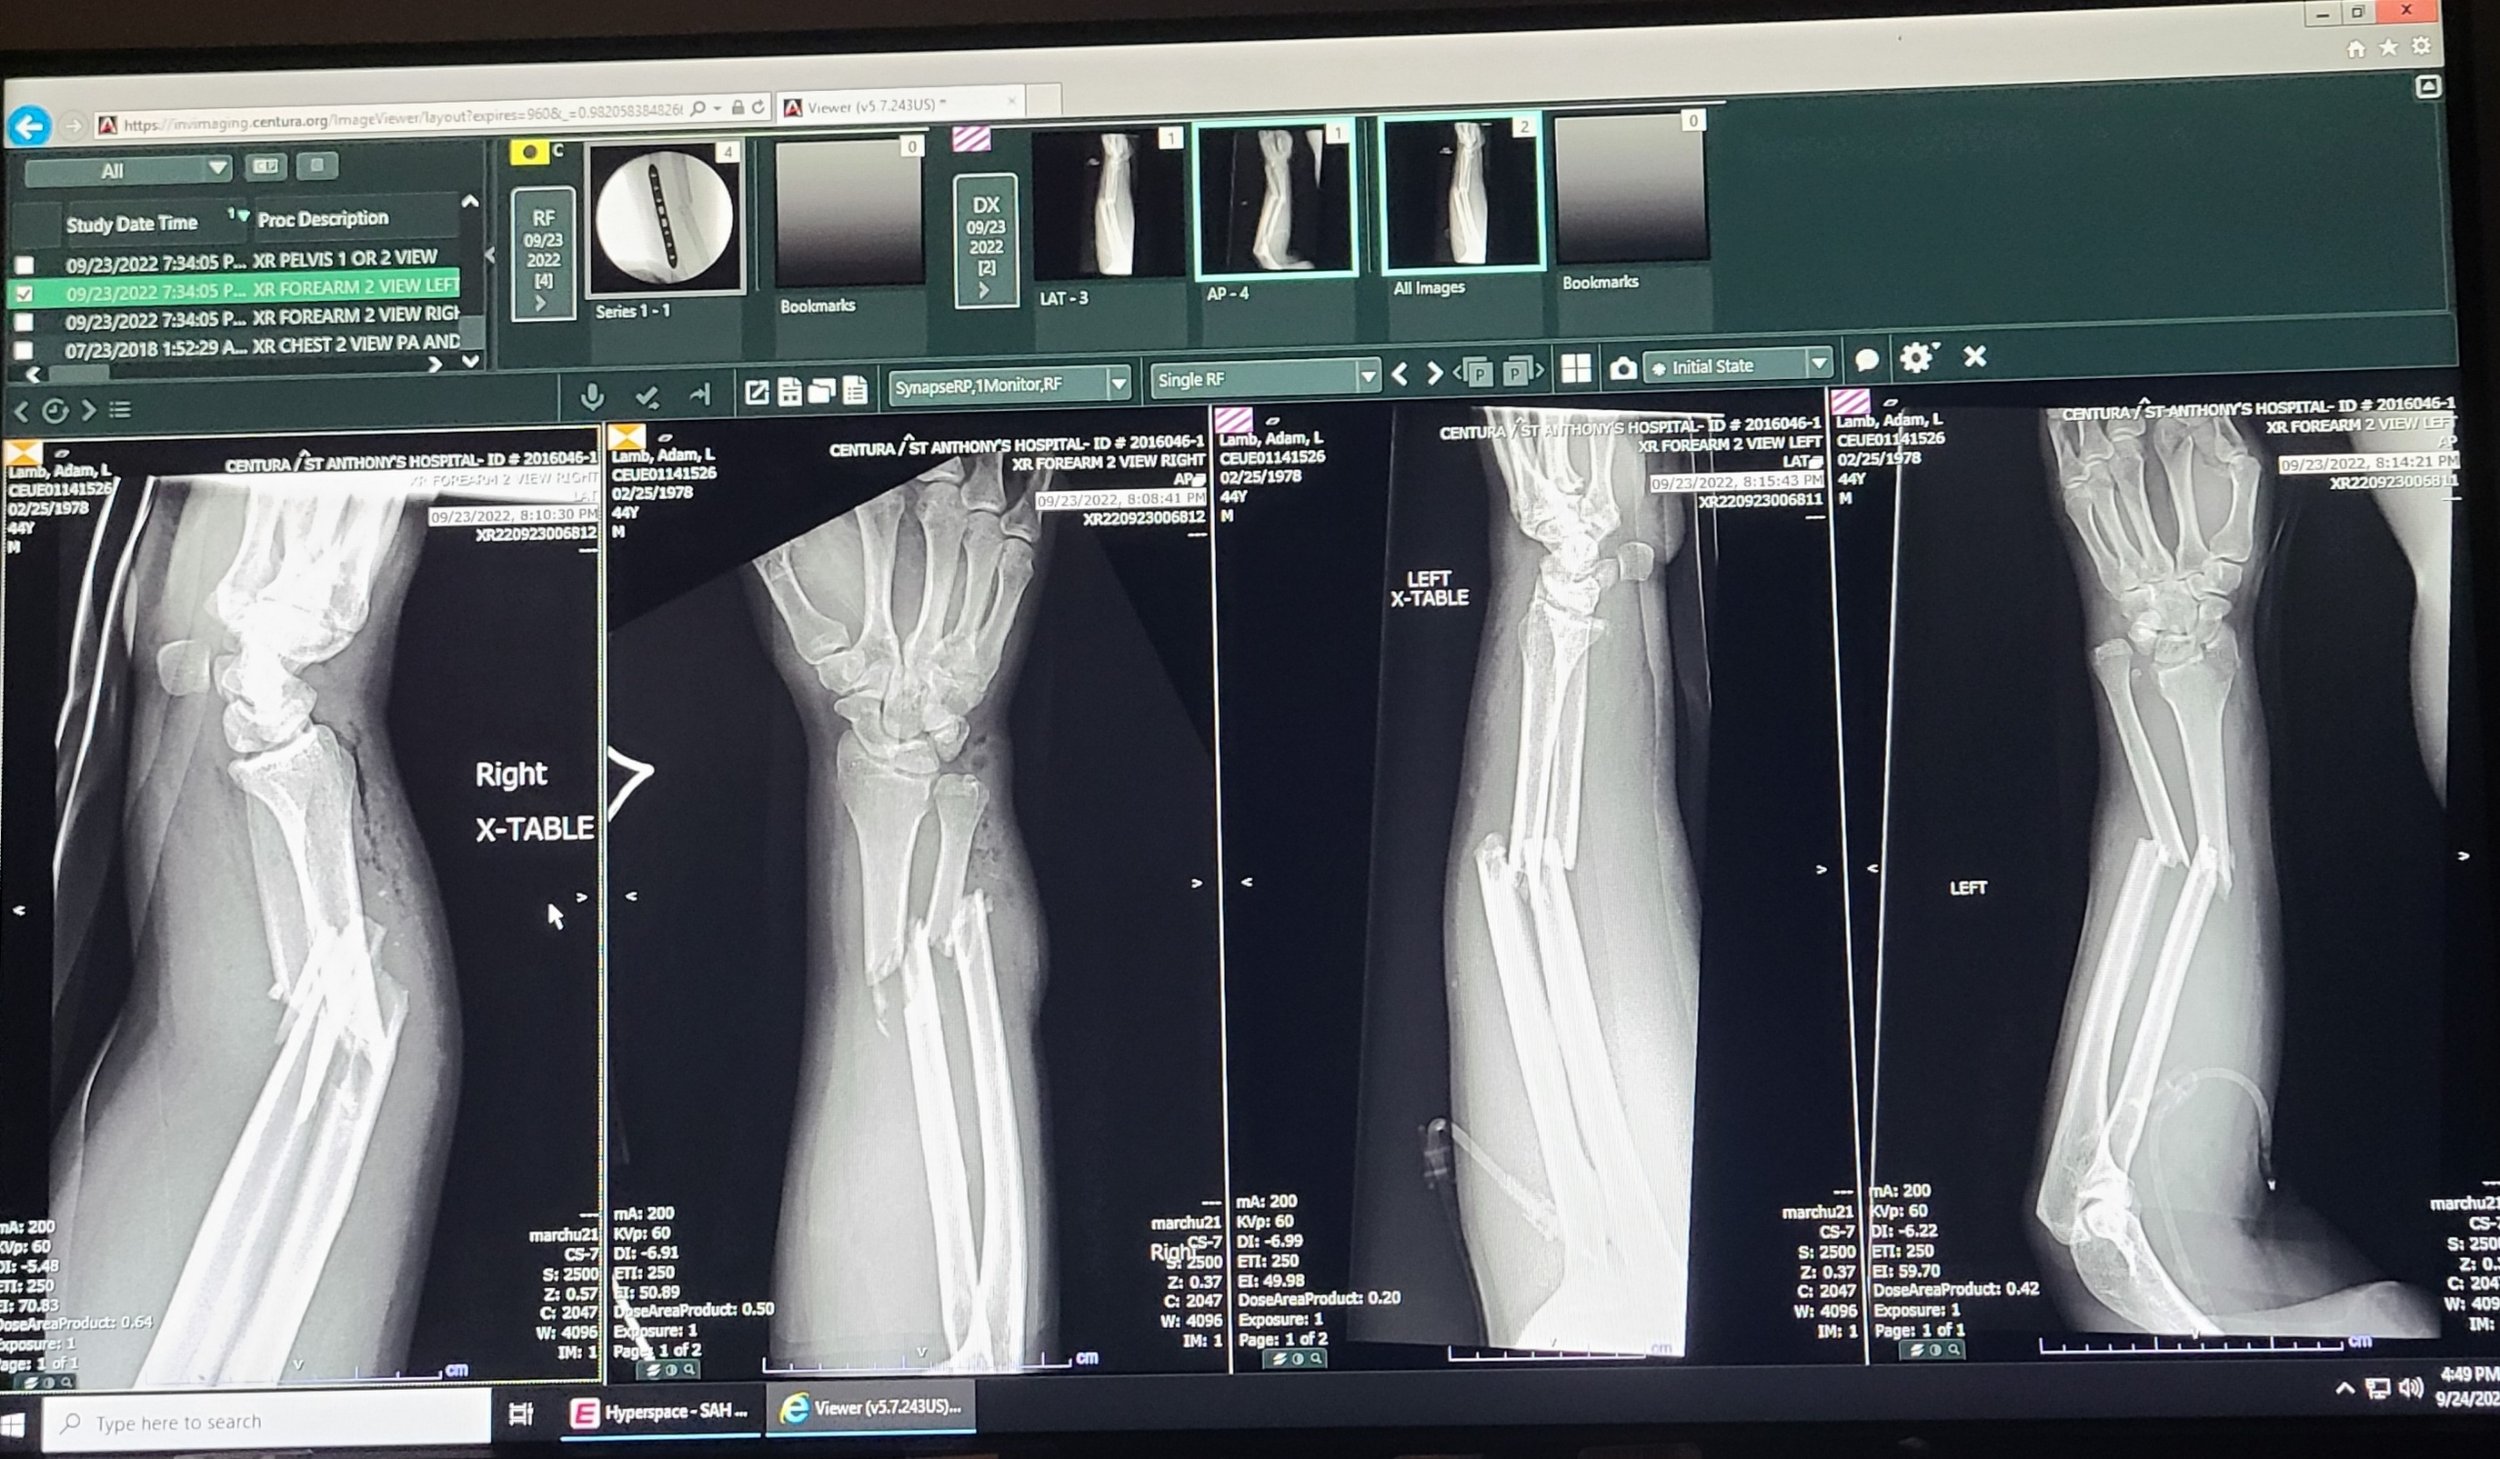

On a mountain road on Colorado’s Guanella Pass, motorcyclist Adam Lamb spots a moose stepping out of the brush. Two seconds later, he’s airborne, both arms broken and stranded off the road without cell service. Just behind him is Roger Matthews—a board-certified physician, search-and-rescue volunteer and also an ADV Rider—who arrives and immediately begins managing the scene. In this episode, Adam recounts the moments leading up to the motorcycle crash while Roger explains how he approached scene safety, organized bystanders, and assessed Adam’s injuries as they waited for help to arrive. We explore wildlife hazards, speed and stopping distance, emergency braking, and why first aid training and preparation can make a critical difference when riding remote roads.